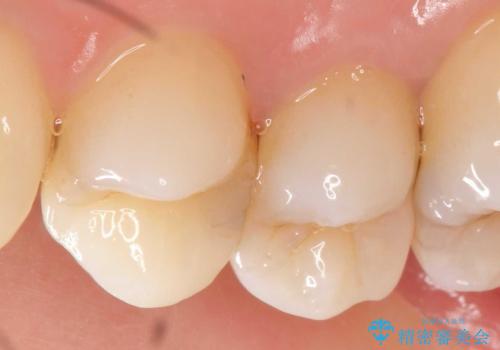

マイクロスコープで神経を保存できるよう丁寧に虫歯を除去したのちセラミックインレーにて高精度な修復を行っていきます。

- 14万円(emaxインレー×2)費用は治療当時の料金となります

セラミック治療は精密な歯牙形態の形成、シリコン印象により高い精度と審美性・予知性が達成されます。